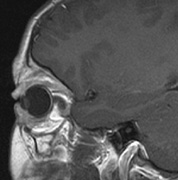

PANCREAS. Pancreatic lesions may be nonsecretory (most commonly cysts or cystadenomas) or secretory (islet cell tumor).179 In one study of 52 patients, 56% (29 patients) were found to have pancreatic lesions. The majority (19 of 29) had cystic changes only (Fig. 17C). Pancreatic lesions were the only abdominal manifestation of disease in 6 of 52 patients.180 In a separate study, pancreatic cysts did not show significant progression on follow-up examinations over an average period of 5 years.181 Like pancreatic cysts, islet cell tumors appear to be frequently asymptomatic.182 EPIDIDYMIS AND BROAD LIGAMENT. Papillary cystadenomas of the epididymis are typically benign and asymptomatic. In one study, about half of patients were affected.183 Papillary cystadenomas of the broad ligament are thought to be the female equivalent of papillary cystadenomas of the epididymis.184 OPHTHALMIC FEATURES VHL syndrome does not appear to have significant anterior segment manifestations. Posterior Segment Retinal capillary hemangiomas are among the most frequent and earliest manifestations of VHL syndrome. Most patients present between 10 and 40 (mean age of 25) years of age and 5% present before age 10. Overall, retinal capillary hemangiomas affect about 60% of individuals with VHL syndrome. Development of new retinal capillary hemangiomas after age 60 years is unusual.169,170 Retinal capillary hemangiomas (Fig. 18) may be the only manifestation of the syndrome,185 and typically involve the midperipheral temporal retina.186 A pair of dilated and tortuous retinal vessels (artery and vein) classically supply the vascular tumor. Without fluorescein angiography, it may be difficult to distinguish artery from vein on fundus examination.170